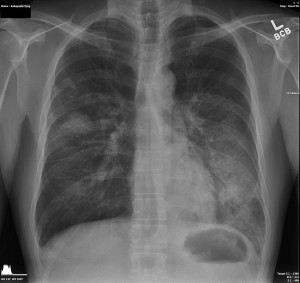

So I took a bunch of NyQuil, packed my things, and went to Paris! And that’s how I developed double pneumonia. I don’t think it was Paris per-se but the 11-and-a-half-hour flight, lack of sleep, jet lag, and all the running around to get to where we were staying. Apparently the body has limits.

- Modern medicine is amazing. I managed to make it to a clinic back in the States and they were like, “Yup, you’ve go pneumonia, like, rilly bad.” Then they shot me in the butt with antibiotics and I started to feel a little better immediately. I almost wept. Then they prescribed a bunch more stuff and I finally started to recover.